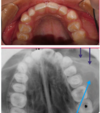

What is this radiographic finding?

Periapical Cysts

►Would need to test both teeth for vitality.

What is this radiographic finding?

Periapical Cyst

What is this radiographic & clinical findings?

Periapical cyst

shows inflammation at site

abscess developed fistula tract thru

soft tissue. Pt will have pain until

pressure is released

What are these radiographic findings?

Residual Cysts

What is the radiographic finding?

Residual Cyst